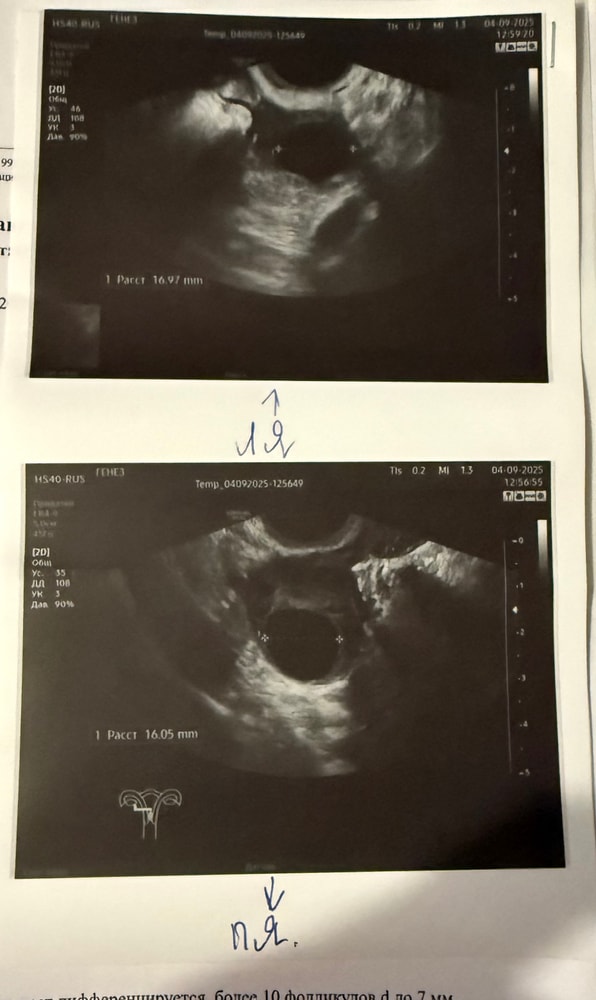

04.09. (15 ДЦ), в ЛЯ ДФ 17 мм в ПЯ ДФ 16 мм. Эндометрий 7,8 мм, трёхслойный.